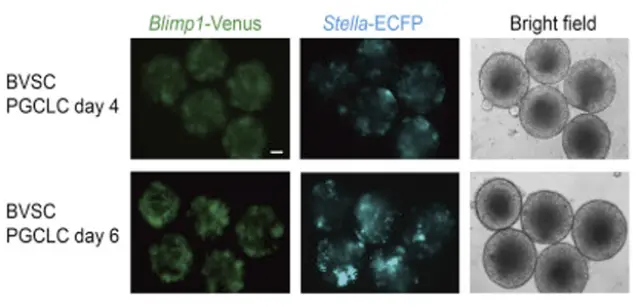

El primer paso de este procedimiento consistió en exponer a las células madre embrionarias de ratón a distintos compuestos químicos para convertirlas en células germinales primordiales. Después, los investigadores procedieron exponiéndolas a hormonas sexuales como la testosterona y a otras células testiculares. Como consecuencia, se cumplieron con las condiciones biológicas necesarias para que la meiosis tuviese lugar con normalidad.